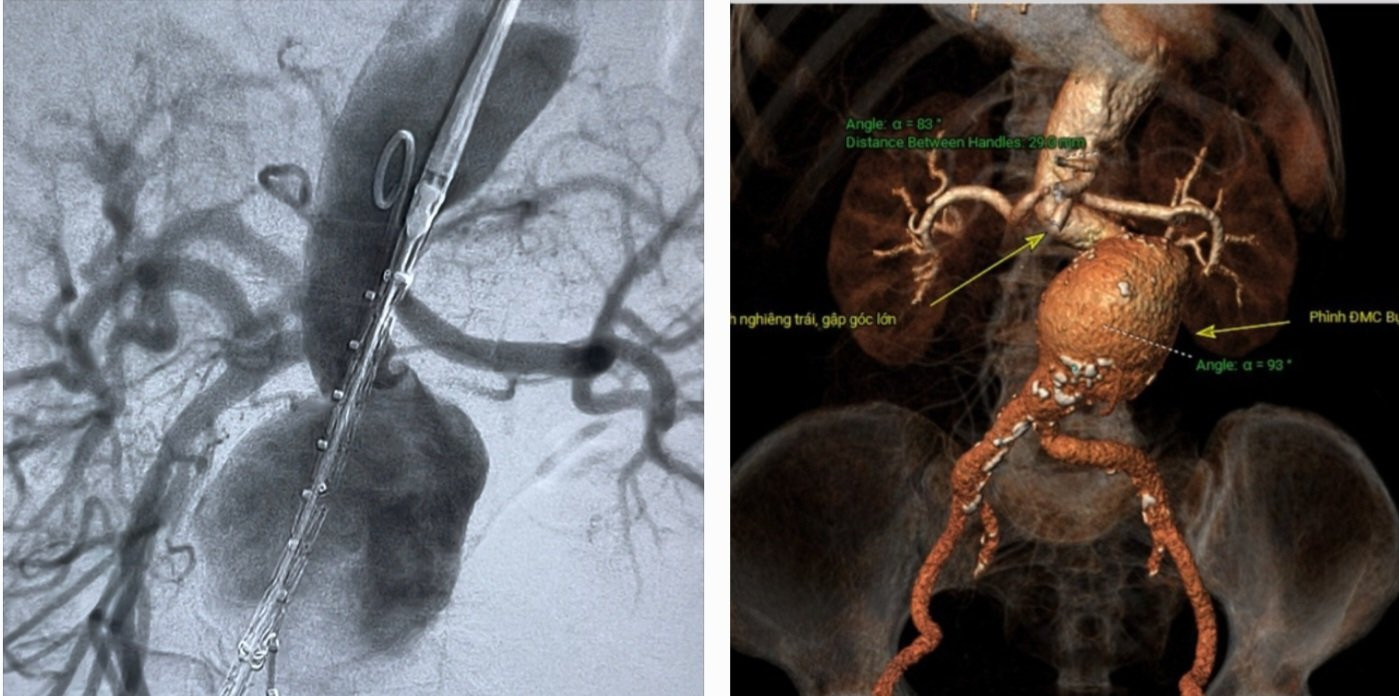

Qua thăm khám và xử trí cấp cứu ban đầu, các bác sĩ chẩn đoán bệnh nhân bị sốc do động mạch chủ ở bụng bị phình lớn, nguy cơ vỡ cao. Sau đó, bệnh nhân được siêu âm bụng và chụp CT để theo dõi.

Tối cùng ngày, cụ bà được chuyển tới trung tâm can thiệp tim mạch. Tại đây, Tiến sĩ Hồ Anh Bình, Trưởng kíp can thiệp cùng nhiều nhân viên y tế đã tiến hành đặt stentraft, cấp cứu thành công cho nữ bệnh nhân M.